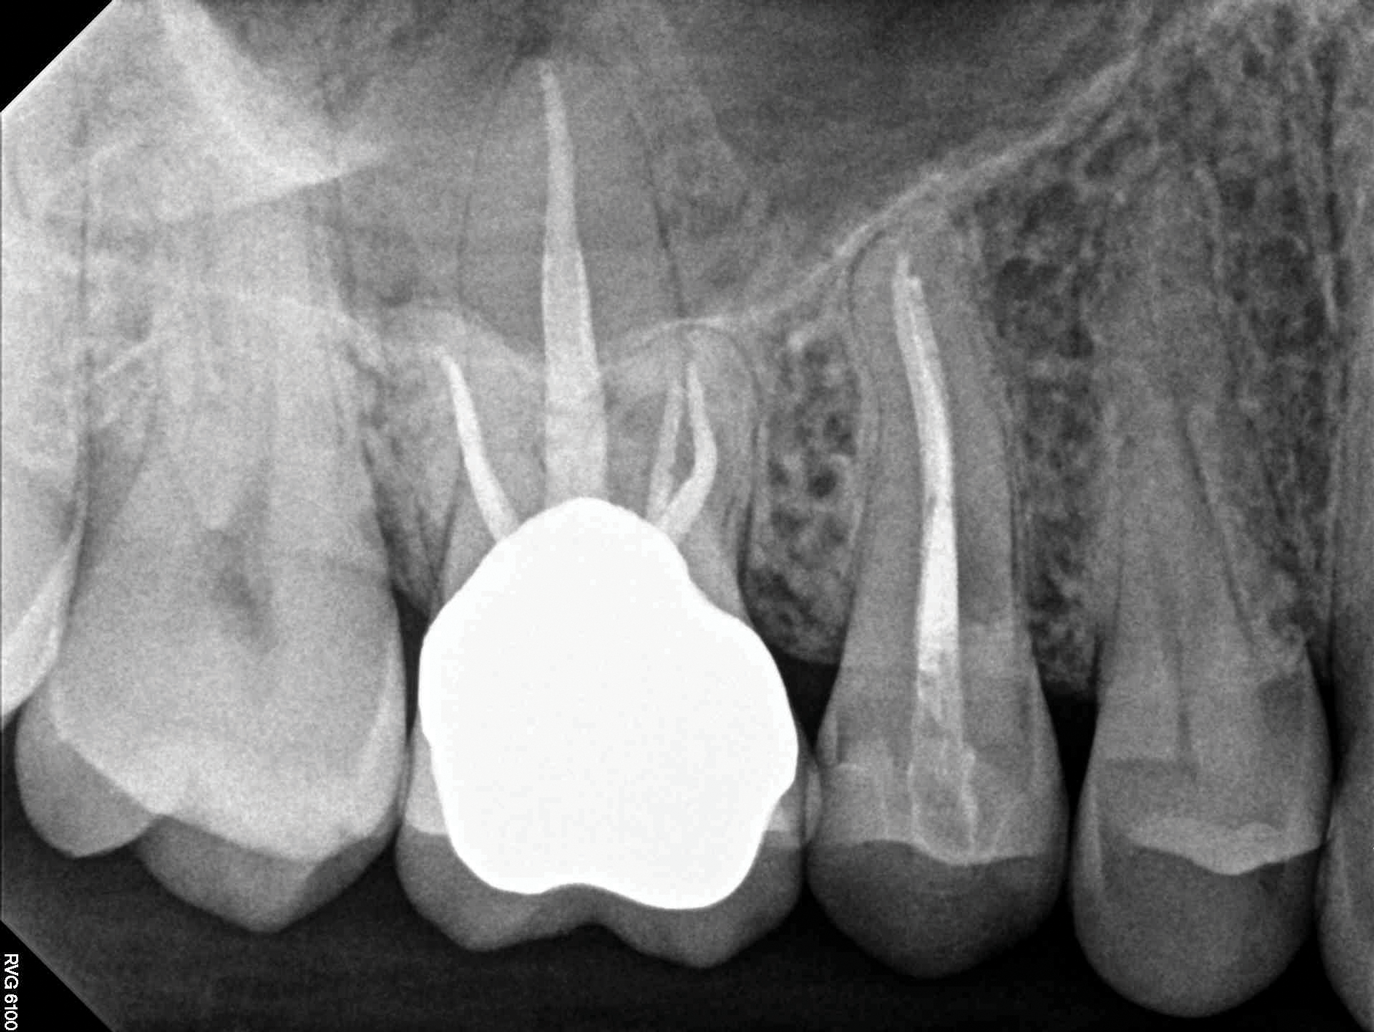

(1.) Preoperative CBCT scan showing Class 2 ECR defects on teeth Nos. 3 and 4 that were surgically accessible.

Figure 1

(2.) NSRCT, which had previously been completed on tooth No. 3, was also completed on tooth No. 4 prior to initiating surgical repair of the ECR lesions because it exhibited signs and symptoms of irreversible pulpitis.

Figure 2